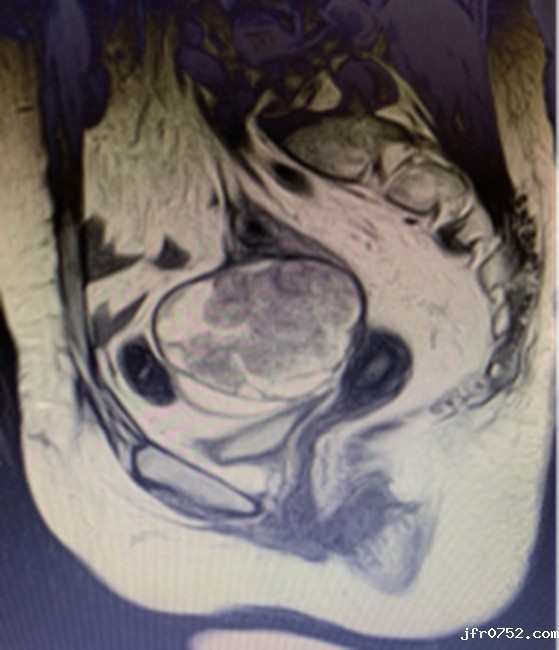

(经详细检查确定,童女士腹腔粘连较重,肿瘤位于盆底,直径10cm大小,与周围肠管,膀胱,输尿管,血管,神经紧密相连,广泛粘连。)

(手术切除透明细胞癌实体瘤大小约8*8.5*9cm,被覆部分乙状结肠肠管,结肠带,脂肪组织,残端宫颈,盆底周围软组织、血管等。)